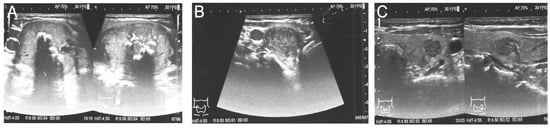

Because PHEO was suspected, the 24 h urinary test was repeated, showing normal concentrations of metanephrine. Ultrasound (US) of the thyroid gland revealed two solid hypoechogenic lesions in the upper part of the right lobe, the first one measuring 35 × 29 × 41 mm with macrocalcifications, and the second measuring 22 mm in maximum diameter without calcifications. US also showed a hypoechogenic lesion, measuring 9 × 7 × 9 mm, in the left lobe (Figure 2), but no lymph nodes suggesting regional metastases. A risk of malignancy of each thyroid nodules was estimated according to the EU-TIRADS classification system [13]. A chest X-ray was normal, whereas abdominal computed tomography (CT) revealed a focal lesion, measuring 12 × 9 × 13 mm, in the left adrenal gland, with non-contrast and contrast-enhanced attenuation levels of 24 and 78 Hounsfield units, respectively (Figure 3).

Because CT imaging did not result in a clear exclusion of PHEO, magnetic resonance imaging (MRI) with contrast enhancement was performed, showing segmental thickening of the medial branch of the left adrenal gland and a solid focal lesion, measuring 11 × 9 mm and with well-defined edges, indicative of a low-fat adenoma without any characteristics of PHEO, so additional procedure such as scintigraphy with metaiodobenzylguanidine (MIBG) was not performed. MRI did not reveal any other significant lesions in the abdomen, including the liver. Fine-needle aspiration (FNA) biopsies of the larger nodule of the right thyroid lobe (Figure 2A) and the focus of the left thyroid lobe (Figure 2C) revealed bilateral MTC (Figure 4A). To confirm the diagnosis of MTC, Ctn concentrations were measured in both FNA washout fluids, but Ctn was significantly higher than normal only in the specimen retrieved from the right lobe (15,417.00 pg/mL).

Figure 2. Preoperative ultrasound of the thyroid gland and the EU-TIRADS categories of thyroid nodules. (A) Right lobe, showing the dominant thyroid nodule, measuring 35 × 29 × 41 mm, with macrocalcifications; EU-TIRADS 4. (B) Right lobe, showing a second hypoechogenic nodule 22 mm in width and 16 mm in height; EU-TIRADS 4. (C) Left lobe, showing a hypoechogenic nodule, measuring 9 × 7 × 9 mm, with irregular margins; EU-TIRADS 5.